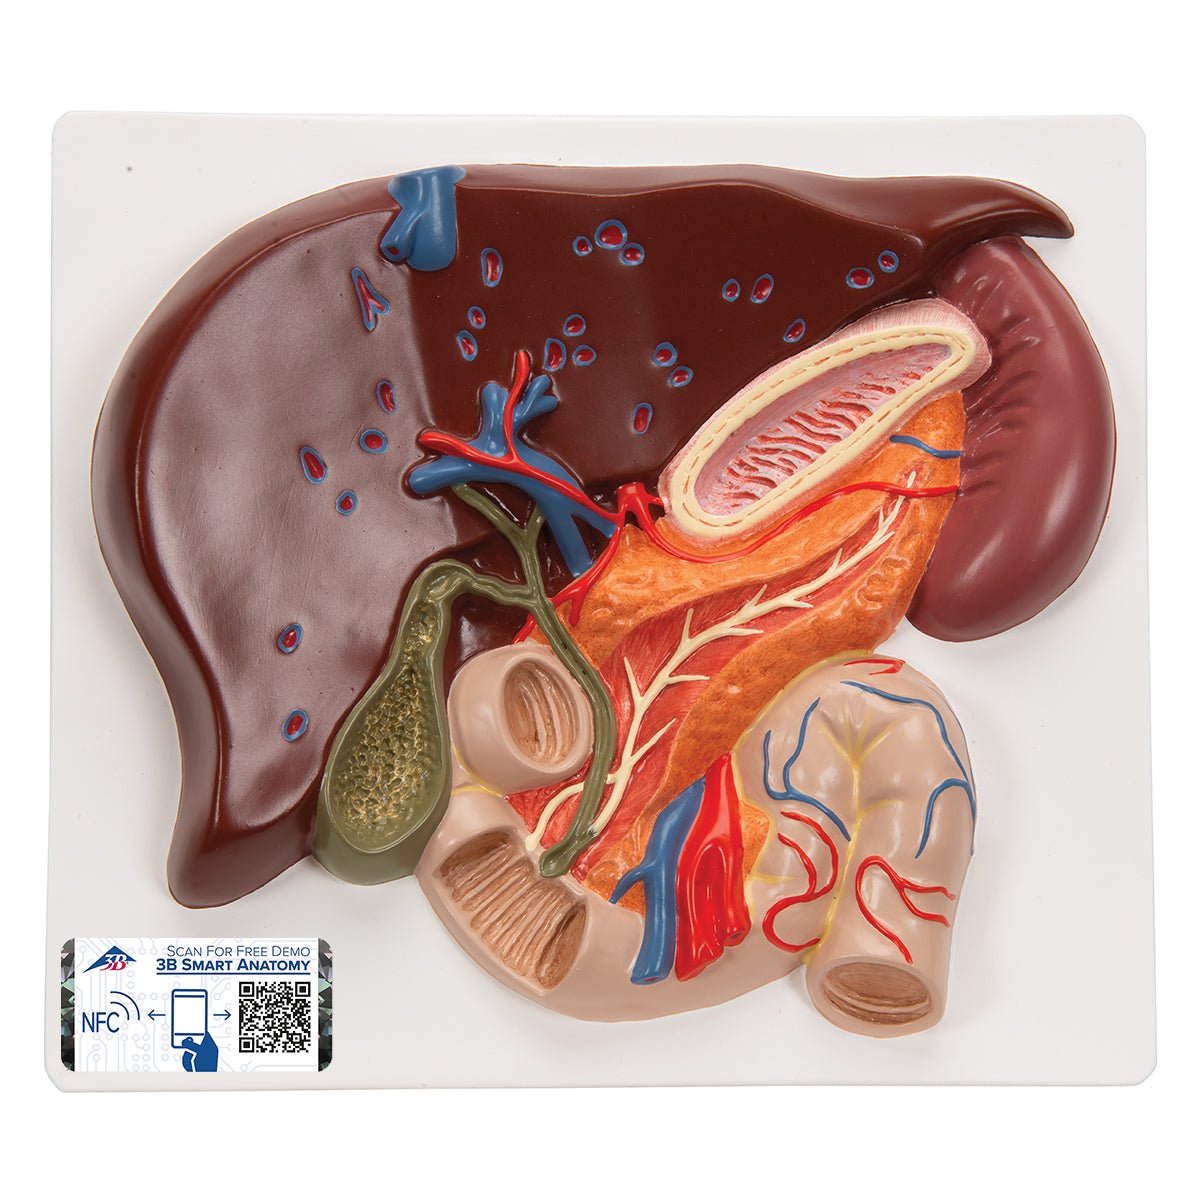

Salg af anatomiske modeller er det bærende element i eAnatomi, selvom vi også bruger mange ressourcer på at udvikle vores egne anatomiske materialer som fx plakater. Anatomiske modeller anvendes til forskellige formål og kan både vise afgrænset væv, organer samt organsystemer. Søger du en simpel model af knoglevæv eller måske en avanceret torso-model baseret på MRI teknologi, kan du finde det hele på eanatomi.com.